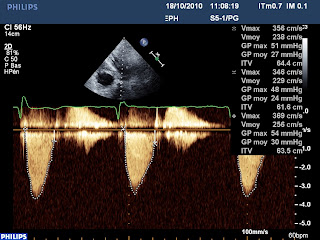

En Doppler continue, on peut obtenir le flux d’IM et celui d’obstacle intra ventriculaire gauche sur la même image :